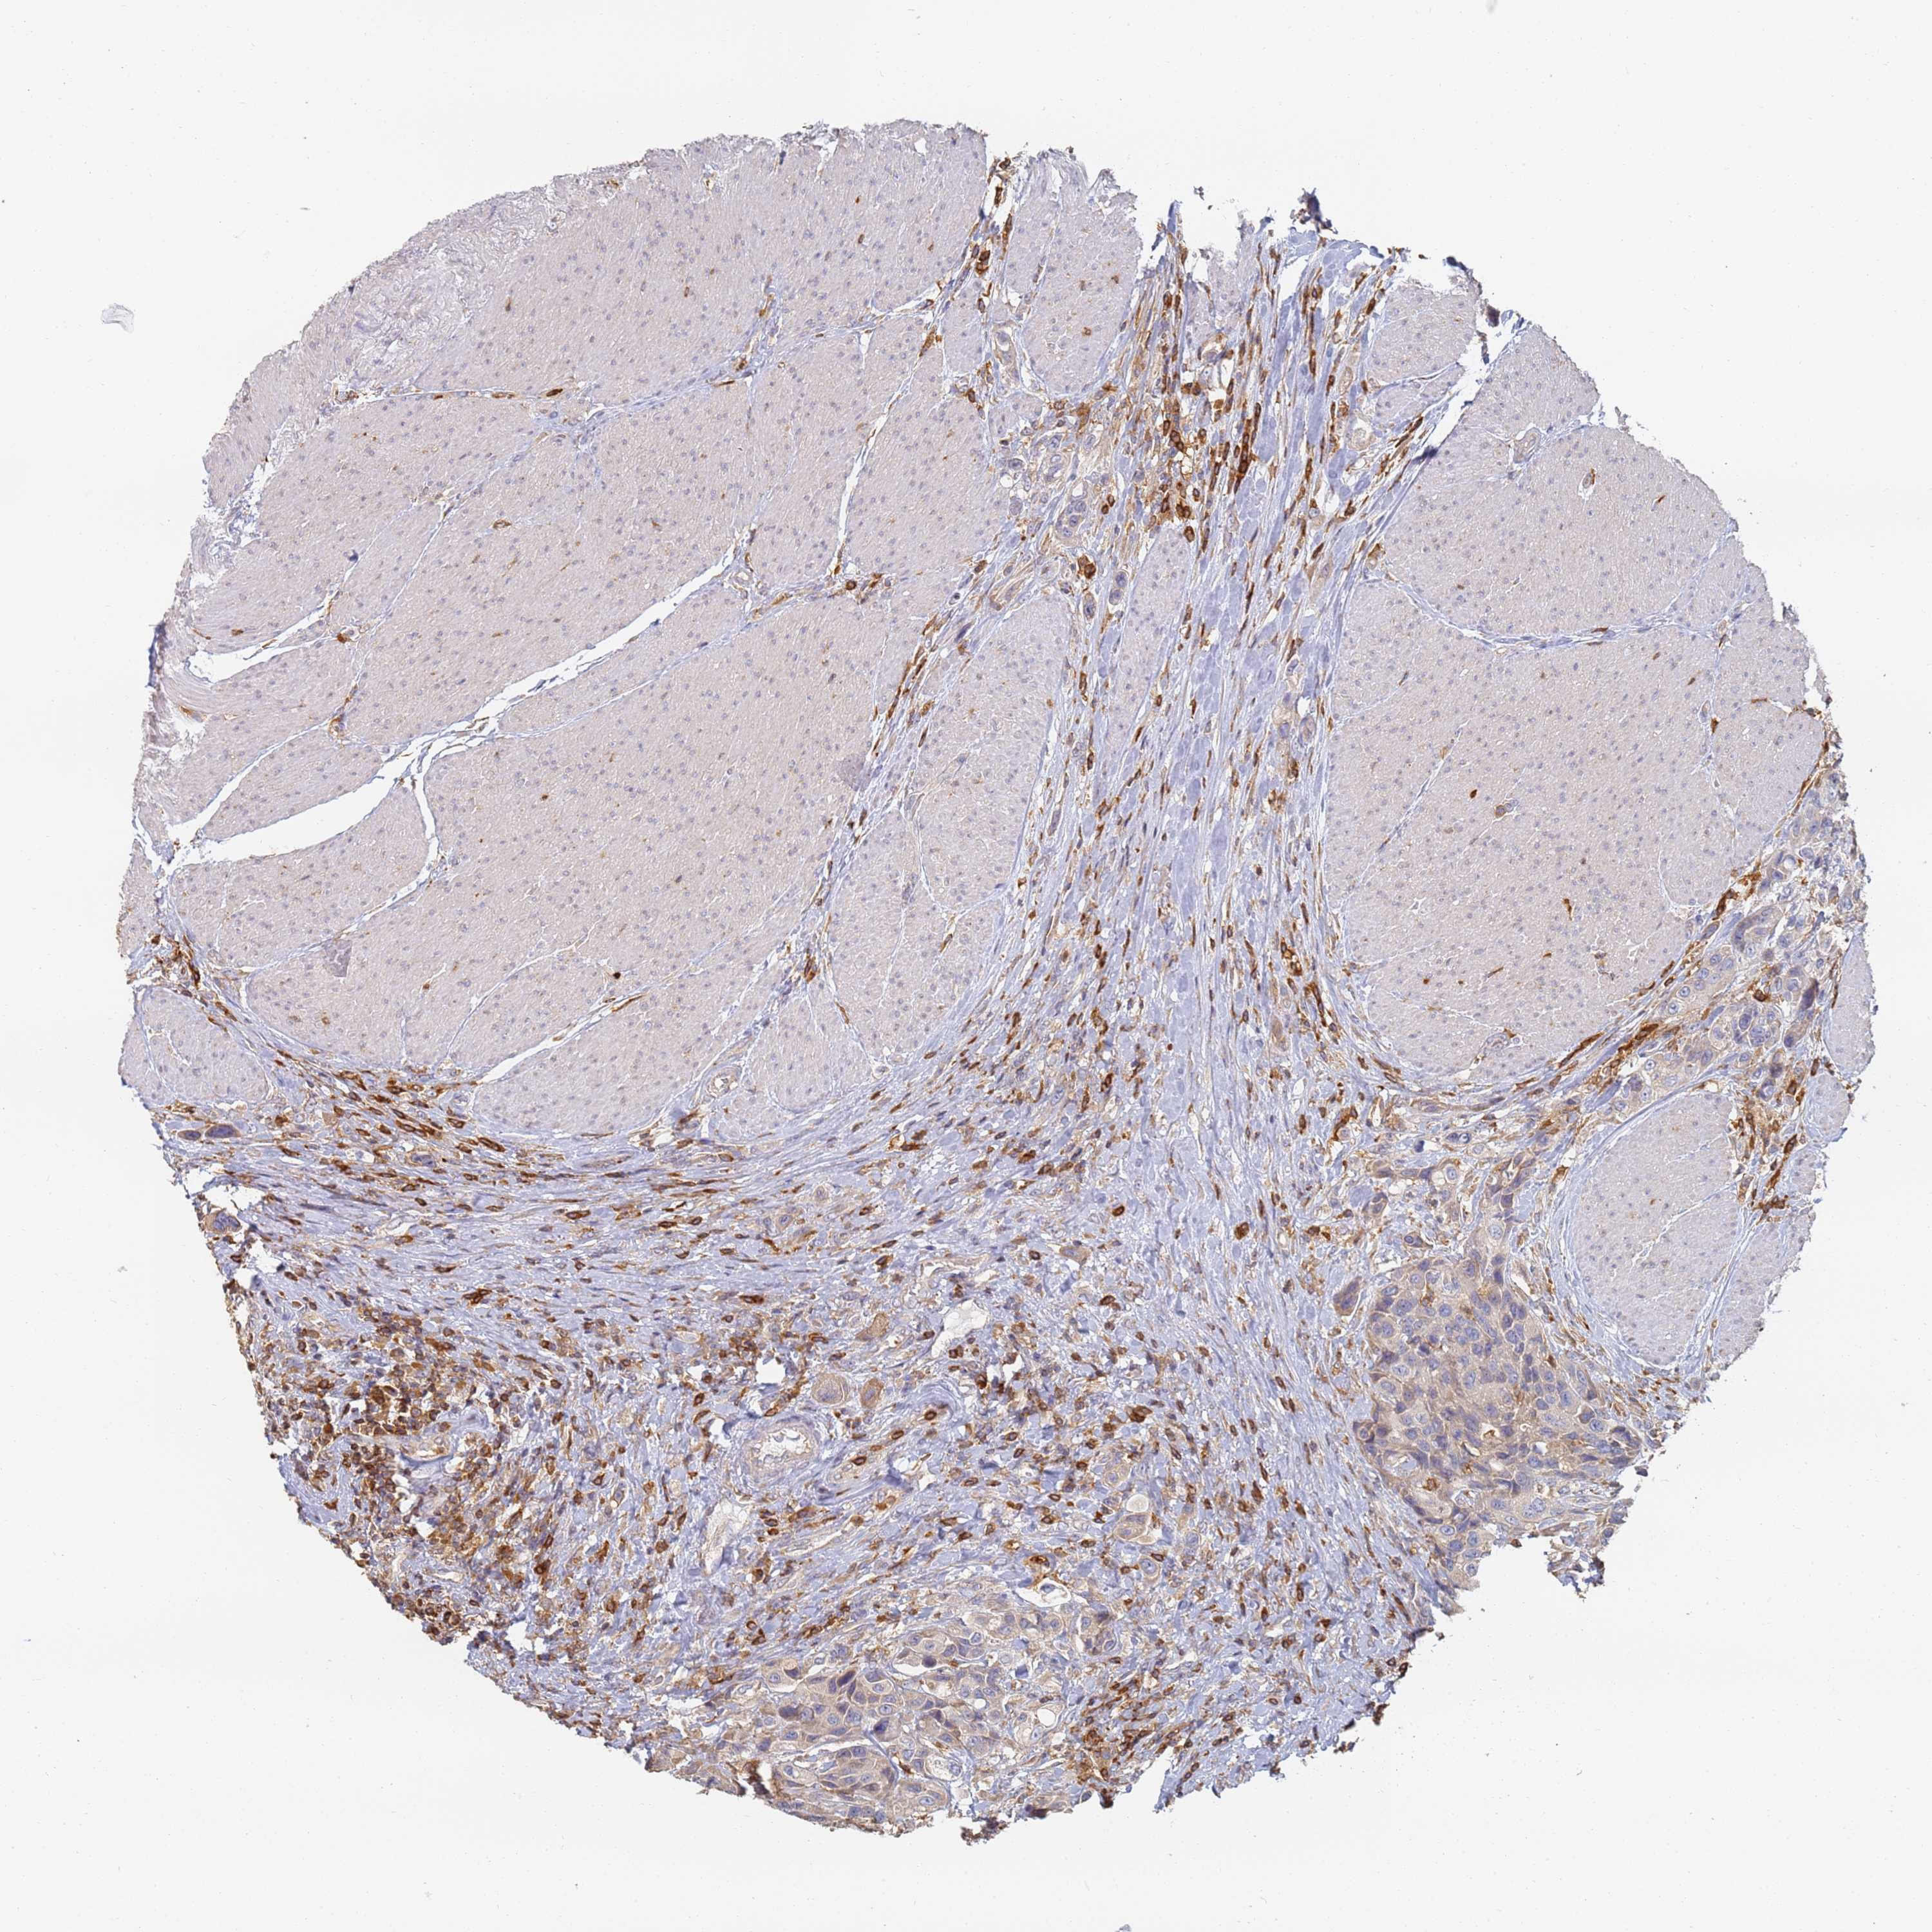

UROTHELIAL CANCER - Protein expressioni

A mouse-over function shows sample information and annotation data. Click on an image to view it in a full screen mode. Samples can be filtered based on level of antibody staining by selecting one or several of the following categories: high, medium, low and not detected. The assay and annotation is described here.

Antibody stainingi

Antibody staining in the annotated cell types in the current human tissue is reported as not detected, low, medium, or high, based on conventional immunohistochemistry profiling in selected tissues. This score is based on the combination of the staining intensity and fraction of stained cells.

Each image is clickable and will lead to virtual microscopy that enables deeper exploration of all samples and also displays staining intensity scores, fraction scores and subcellular localization as well as patient and tissue information for each sample.

Antibody HPA038666

Antibody HPA038667

Urothelial carcinoma, High grade

Urothelial carcinoma, Low grade